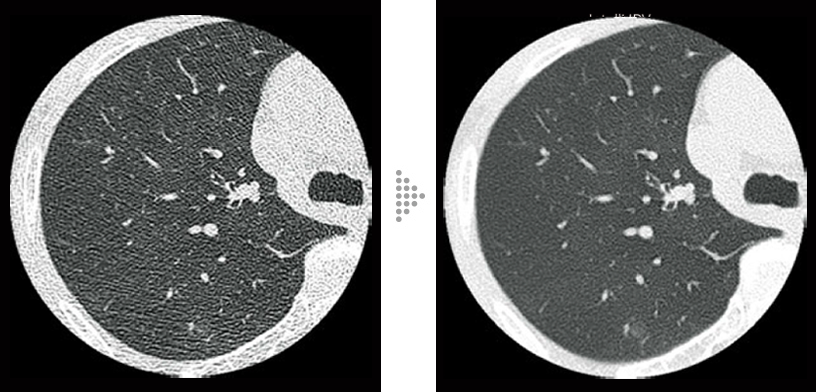

Lung screening (CTDI vol: 2.0 mGy)

Non-tuberculous mycobacteria